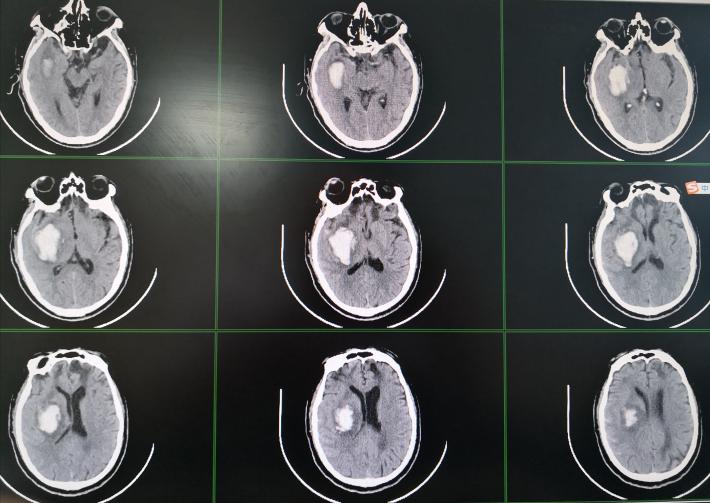

术后复查头部CT:脑内血肿几乎全部清除。

术后第五天,病人自行睁眼,能简单回答问题,右侧上下肢能遵嘱活动。左侧上下肢活动较术前改善。